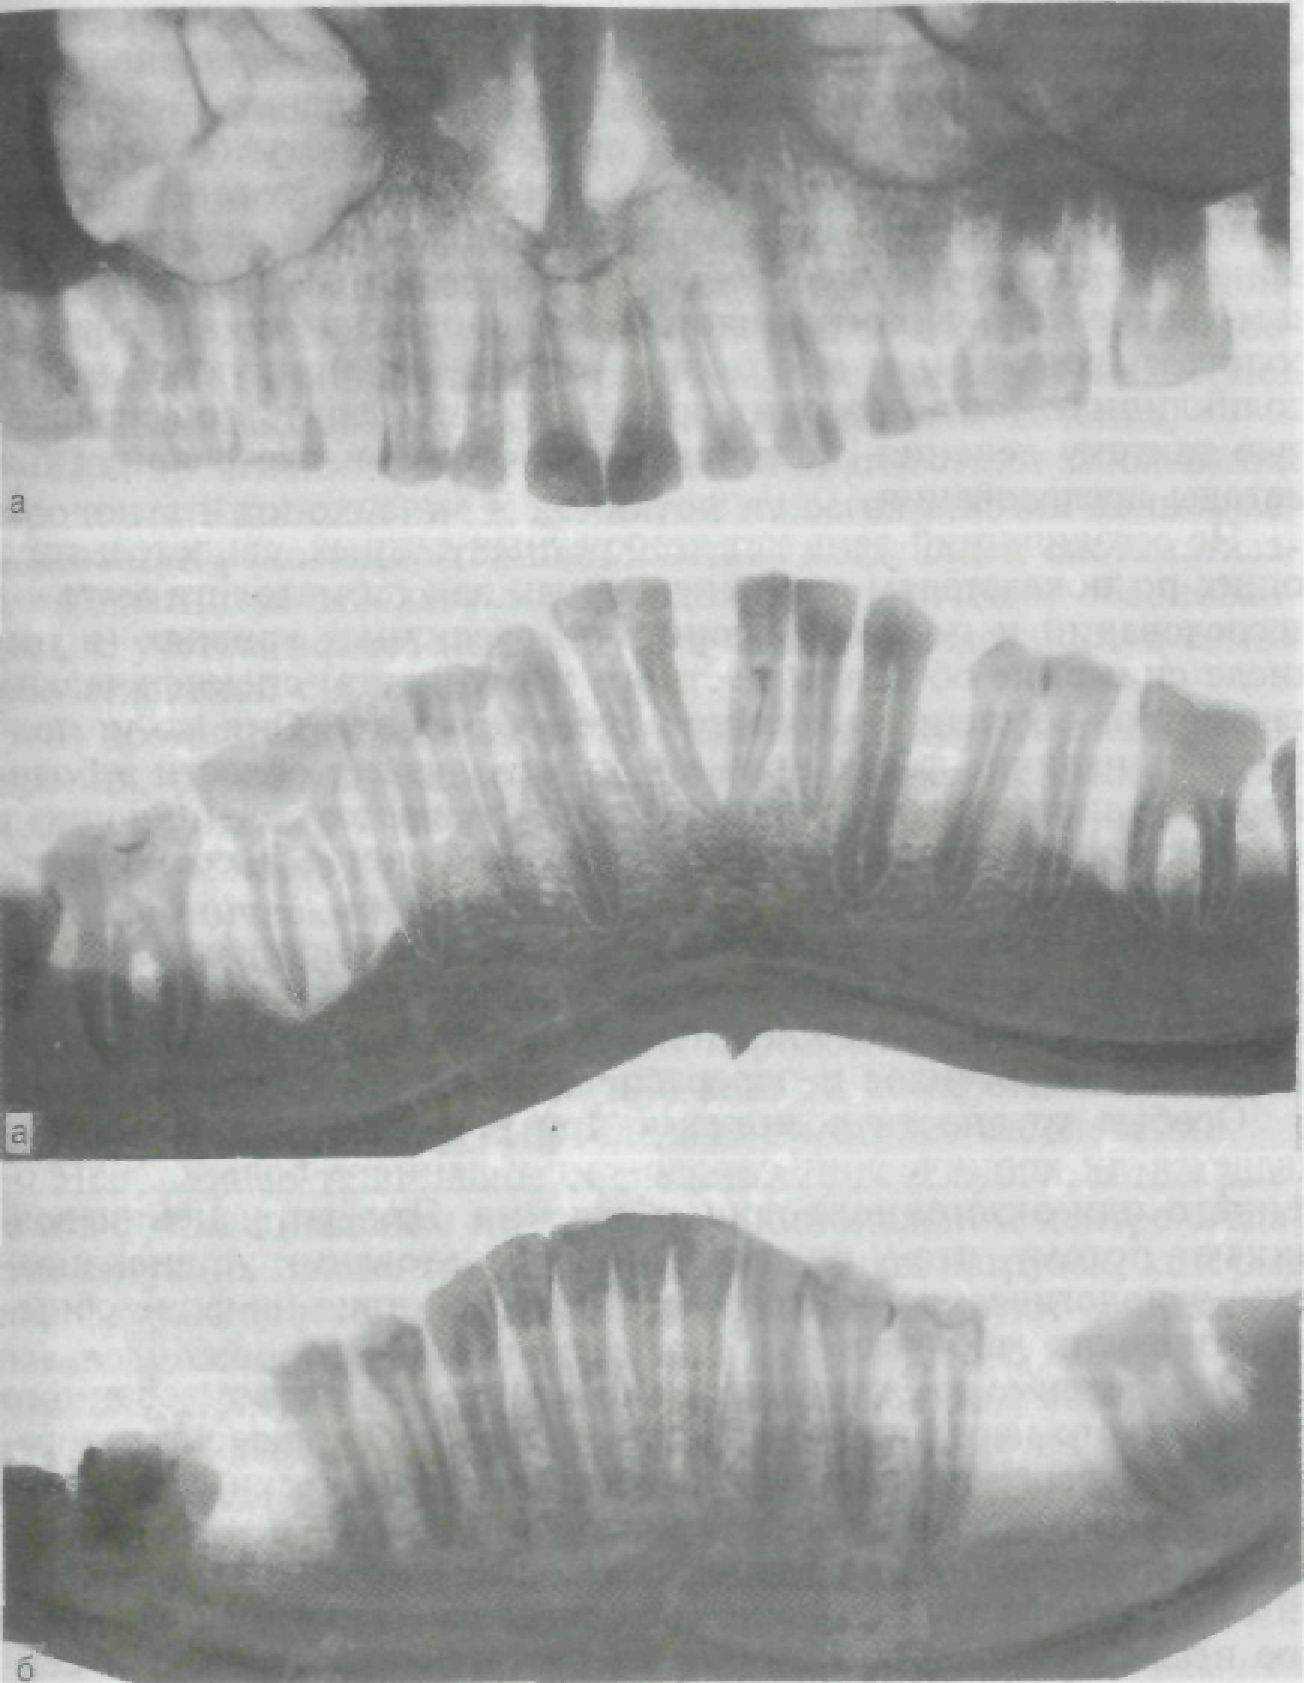

При присоединении к этому заболеванию дополнительно действующих местных факторов, помимо генерализованного поражения, определяется неравномерность степени резорбции тканей пародонта у отдельных зубов или групп зубов. Знание специфики деструктивных процессов под влиянием местно-действующих факторов и целенаправленное обследование общего состояния организма позволяют уточнить не только диагноз, но и тя-

Рис. 159. Дистрофические процессы в костной ткани при генерализованном (а) и локализованном (б) пародонтите.

жесть процесса в зубных рядах и отдельных их звеньях. Диагноз может быть уточнен следующими дополнениями: пародонтальный абсцесс, гипертрофический гингивит, травматический узел в области передних зубов. Фактически эти дополнения к диагнозу следует расценивать как осложнения пародонтита.